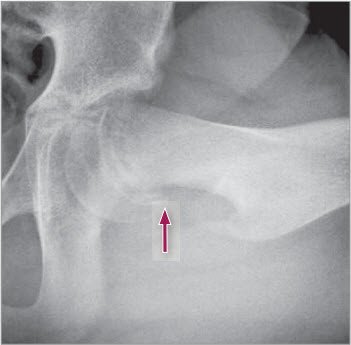

Abrutschen der Kalotte

1 Seitliche (Imhäuser) Aufnahme, links mit deutlichem Abrutschen der Kalotte nach hinten (Pfeil)

chronischer Epiphysiolysis capitis femoris

2 AP-Projektion der linken Hüfte mit chronischer Epiphysiolysis capitis femoris. Die Epiphysenfuge zeigt sich unregelmässig verbreitert und die Epiphysenhöhe vermindert